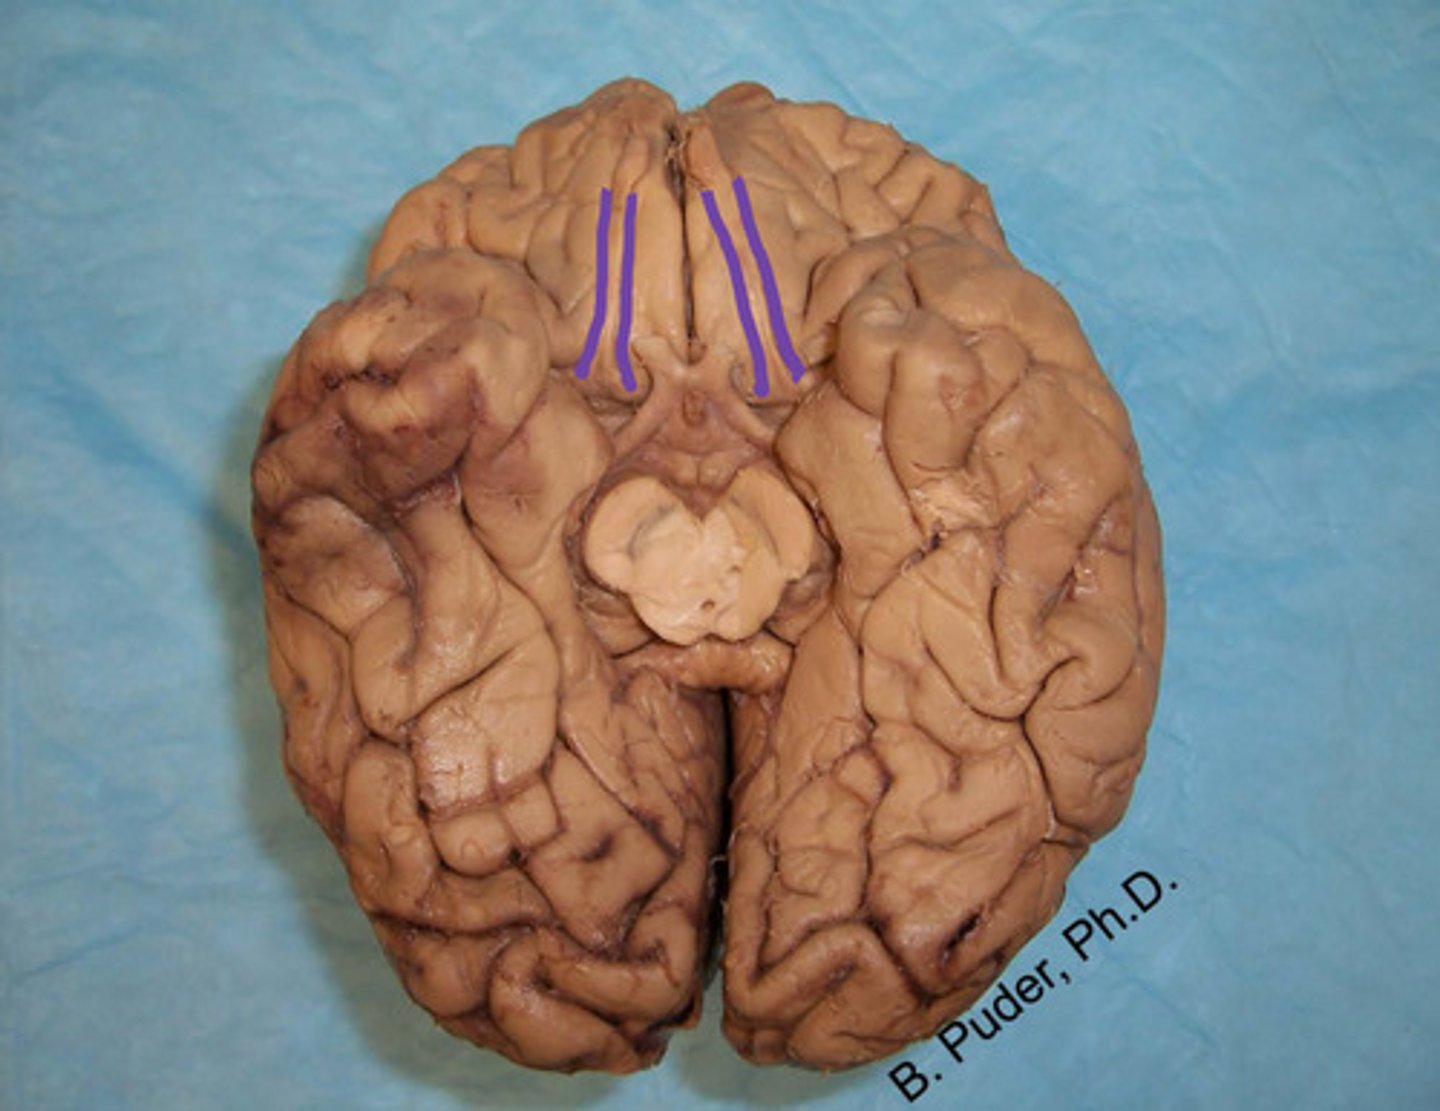

blue - thalamus

purple - hypothalamus

identify the structures

thalamus

identify the structure